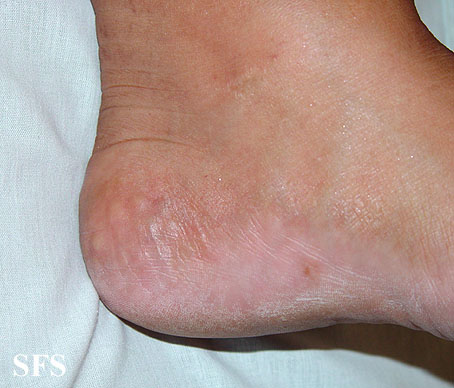

fat herniation